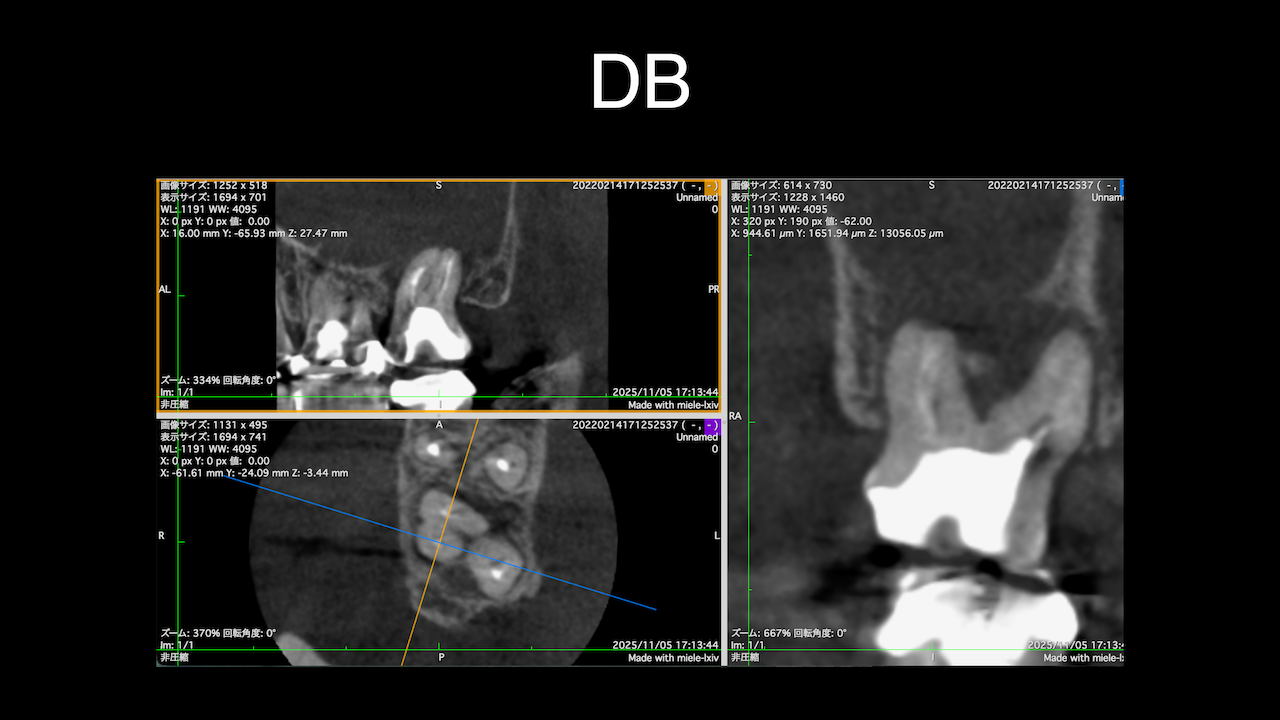

DB根はすでに切断されている。

が、逆根充がなされていない。

DBは根切済みだ。

Pにも病変がある。

ということは、再根管治療だろう。

ただ、予後はGuardedだ。

なぜか?根切がうまく行っていないからだ。

臨床的にDB

3ヶ月経過した。

DBの病変が小さくなっている。

Pは病変が大きくなっていうように見えるがまだわからない。